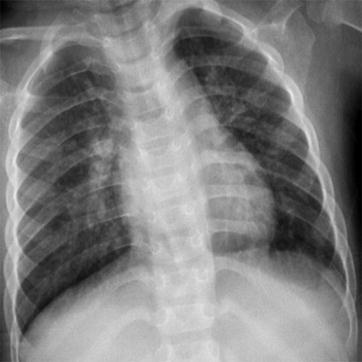

Fig. 23.4.

Adult measles pneumonia. X-ray demonstrates enhanced pulmonary markings at the right lower lung